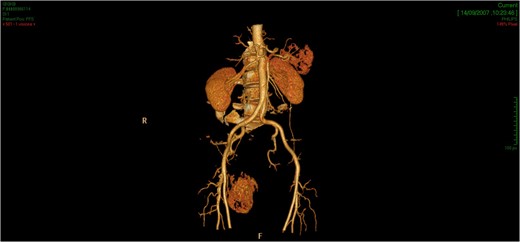

CT showed an hyperintense and inhomogeneous solid lesion taking up the right ischiorectal fossa (maximum diameter of about 10 cm), extended cranially until impressing the wall of the rectal ampulla, with no apparent infiltration (Figs 2 and 3). The lesion presented an intense contrast enhancement, sign of a rich vascularization (Fig. 4).

The CT scan demonstrates a solid neoformation in the right ischiorectal fossa.

The lesion extends cranially until impressing the wall of the rectal ampulla, with no apparent infiltration.

The tridimensional reconstruction shows the rich vascularization of the neoplasm.